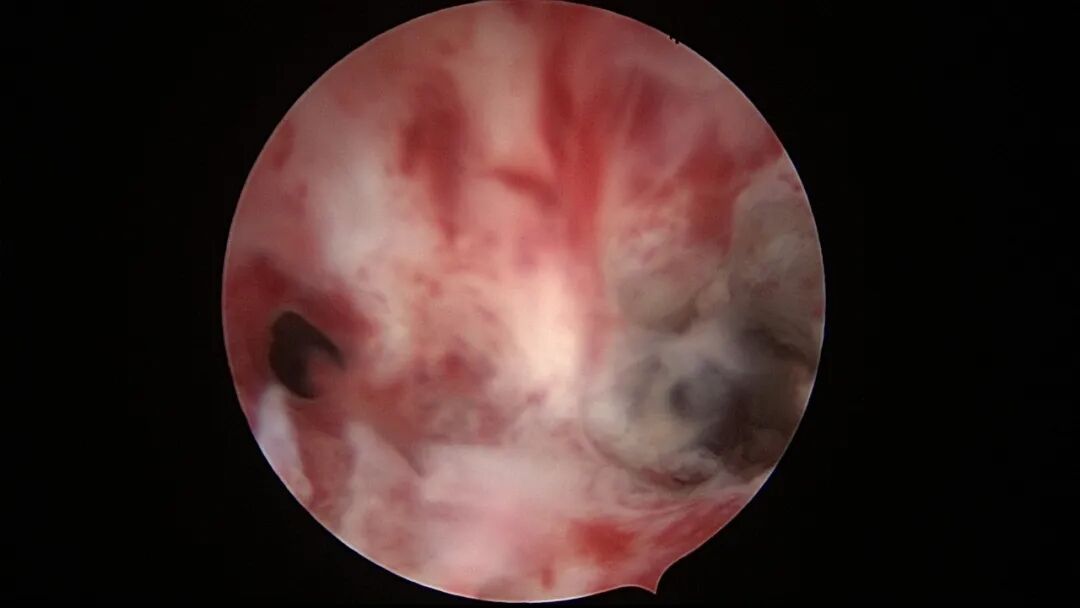

第七次宫腔镜:2025年6月因异常子宫出血、月经淋漓不净10+天,行宫腔镜探查,宫颈管见陈旧血丝,宫腔形态欠规则,宫腔两侧纤维性粘连,宫腔狭小,内膜薄,内膜充血。单极电针分粘,宫腔形态基本恢复正常,左侧输卵管开口显露,右侧输卵管开口不可见。内膜病检为增殖期样子宫内膜伴出血。